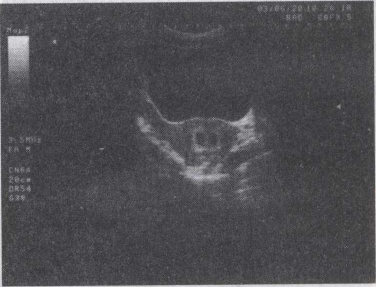

46.女,27岁,停经49天,尿妊娠试验阳性。超声如图所示,最可能诊断为